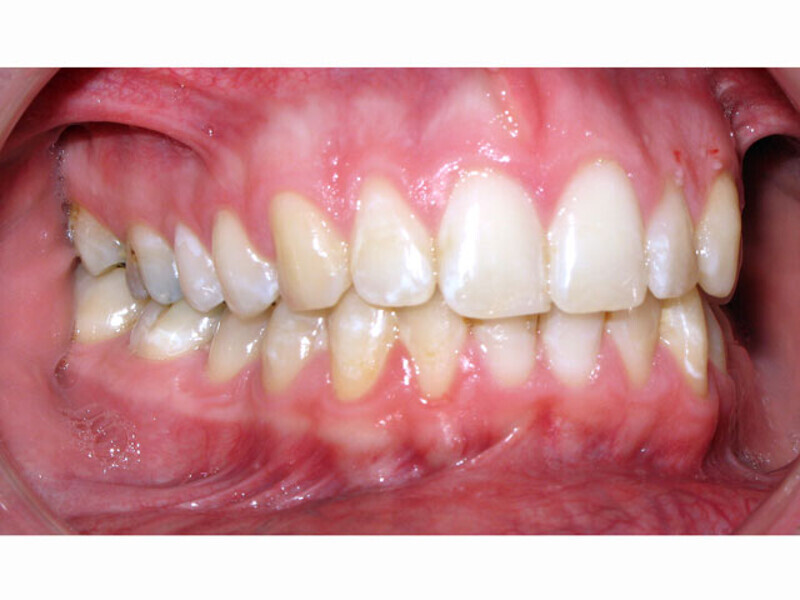

ClearCorrect treatment of crowding